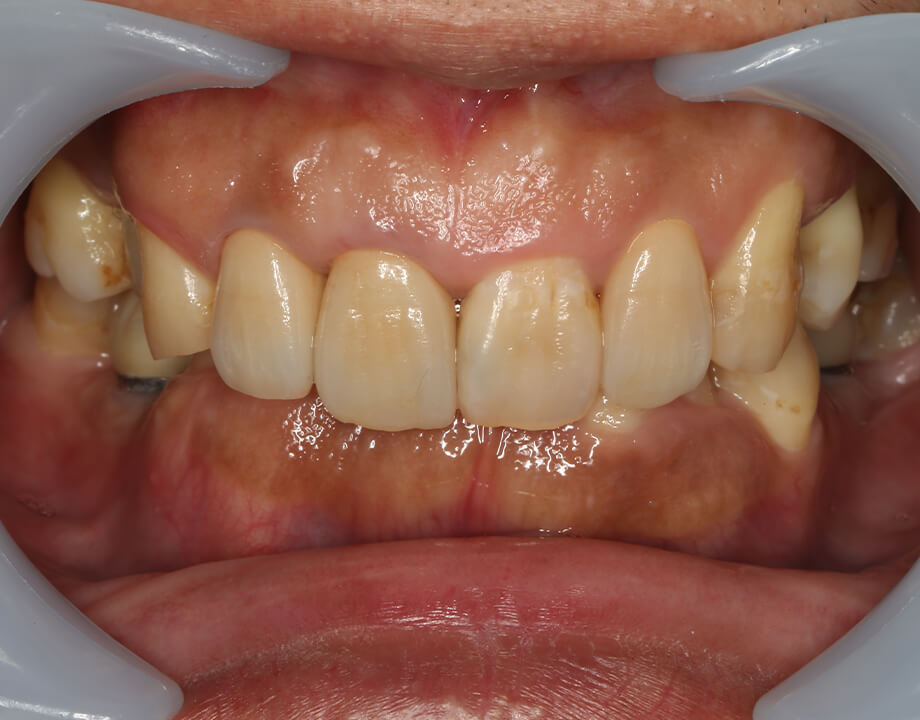

Case 01天然歯

ジルコニアレイアリング